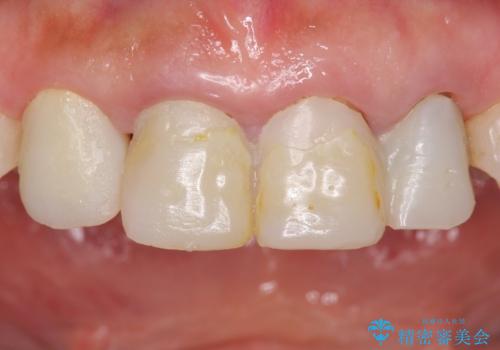

歯と歯の間の虫歯 セラミックインレーでの治療

白くて精度の高いものをご希望されたためセラミックインレーでの治療を行いました。